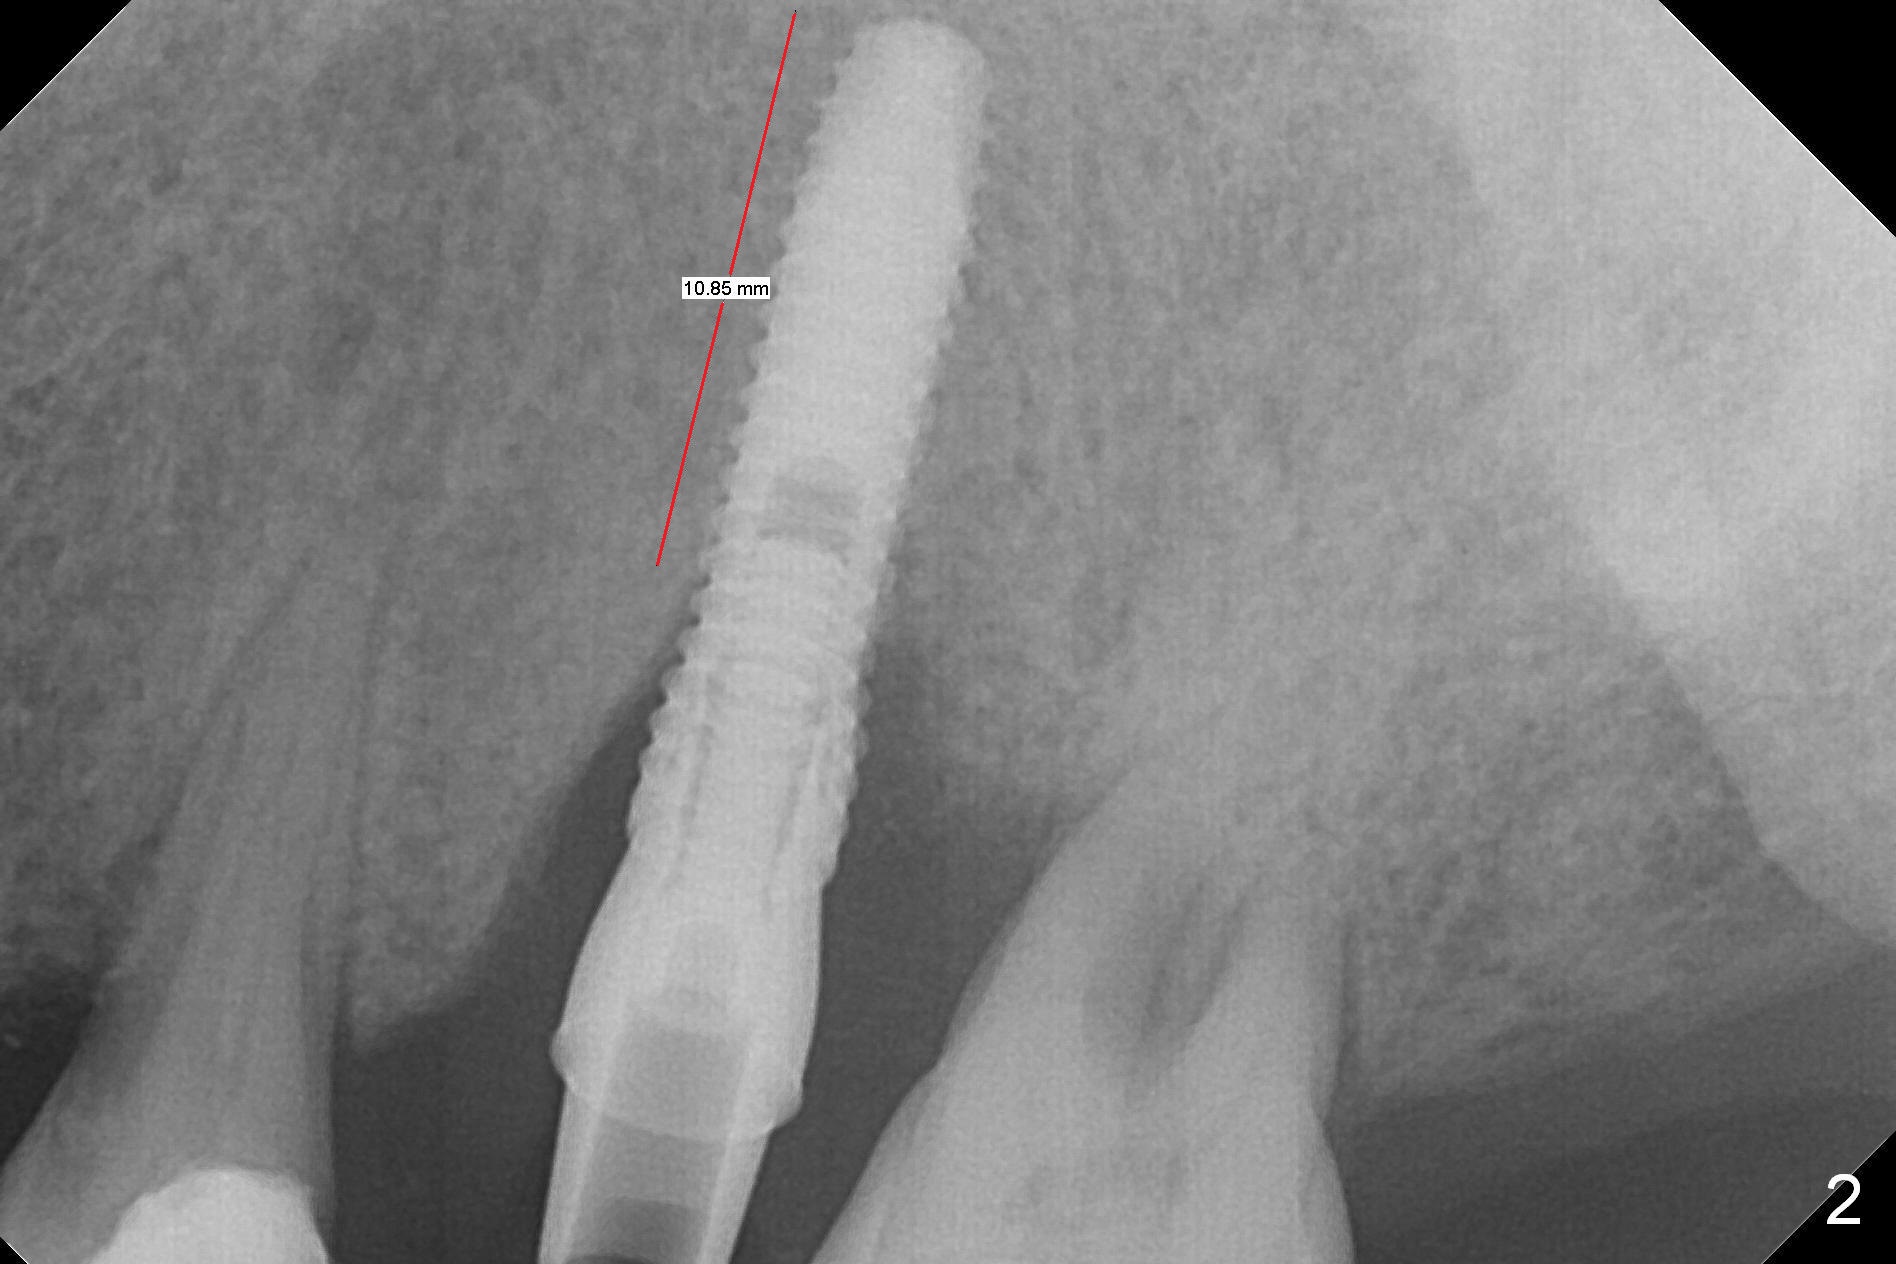

Initial osteotomy depth is 18 mm (Fig.1 green line) with 9 mm in the native bone (red line). The bone density feels to be low. There is at least 2 more mm bone apically (pink line). The depth is increased by 2 mm so that when a 3.8x15 mm implant is placed, there is 10-11 mm implant/bone contact (Fig.2 red line). There is large bony defect (Fig.3 *), which is bone grafted (Fig.4 *). Finally a longer abutment is placed (4.5x5.5(5) in Fig.4 vs. 4.5x4(5) in Fig.2,3). The 5 mm cuff does not look too long buccally (Fig.5) or palatally (Fig.6). To prevent postop buccal gingival overgrowth (2), the buccal margin of an immediate provisional is subgingival (Fig.7-9 *). Bone density between #13 and 14 appears to increase 3 months postop (Fig.10). The implant seems to be equi-crestal (Fig.11 ^). There seems to be more bone growth (i.e., decreasing gap) 6 months postop (Fig.12). Impression is taken. A crown is delivered nearly 7 months postop (08/07/2017). While there is minimal bone loss at #13 and 15 three years and 4 months post cementation, the tooth #14 and 18 are mobile (Fig.13,14).